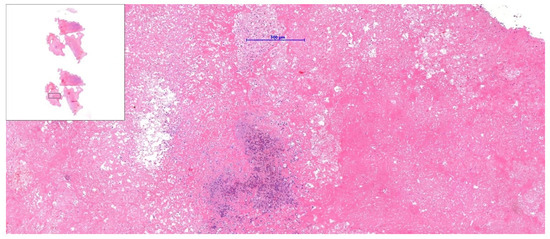

Echocardiography remains a vital part of the initial assessment and monitoring of oncological patients. It allows for proper treatment selection but can also reveal life-threatening complications, including impaired left ventricular function or thromboembolism. It can rarely detect intracardiac masses that require further investigation. In the presented case, a 51-year-old female patient with left-sided breast cancer, who had undergone neoadjuvant chemotherapy, was hospitalised due to a right atrial mass identified via routine transthoracic echocardiography (TTE). Initial anticoagulation therapy showed no clinical improvement. Follow-up TTE revealed a 12 × 19 mm hyperechogenic, mobile mass in the right atrium (RA). Computed tomography angiography (CTA) ruled out pulmonary embolism and revealed that the mass was located close to the tip of the vascular access port. Transoesophageal echocardiography showed that the lesion was not connected to the vascular port. Based on location and mobility, the lesion was most consistent with a cardiac myxoma. After the Heart Team made a decision, endovascular intervention using a vacuum-assisted device was performed without complications. Histopathological examination excluded thrombosis and myxoma, revealing a fibro-inflammatory lesion. A multimodality approach is necessary to assess RA masses. However, even an extensive evaluation could be misleading, so treatment options should always be subject to the Heart Team’s decision. Full article

Figure 1